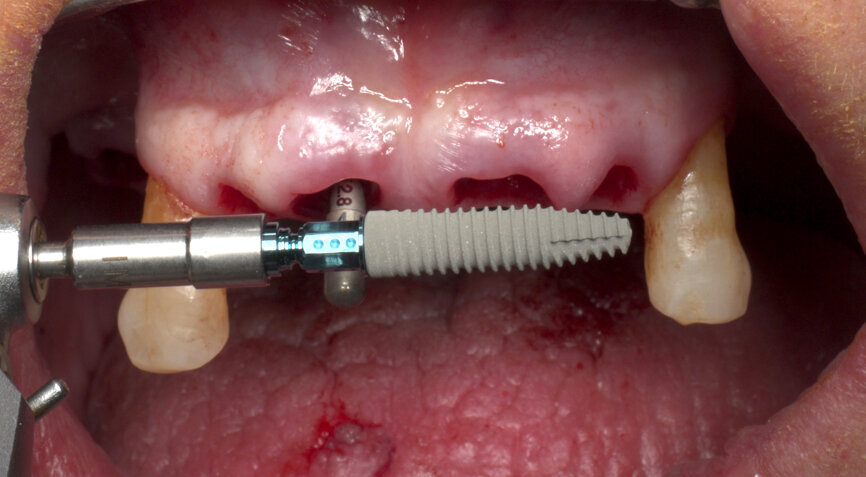

Furthermore, undersized drilling with continuous bone density assessment according to the operator’s own experience is mandatory to achieve the highest insertion torque, taking account of the biological bone situation and the mechanical properties of Roxolid. In this case, six implants (Straumann BLT, Regular Neck, Roxolid, SLActive, four of ⌀ 4.1 mm and two of ⌀ 4.8 mm) were placed with the handpiece at 45 N cm, with a final manual setting and monitoring of the insertion torque (Figs. 5 & 6). Careful orientation of the Loxim orientation marks is mandatory to maintain the desired parallelism of the SRA prosthetic screws.